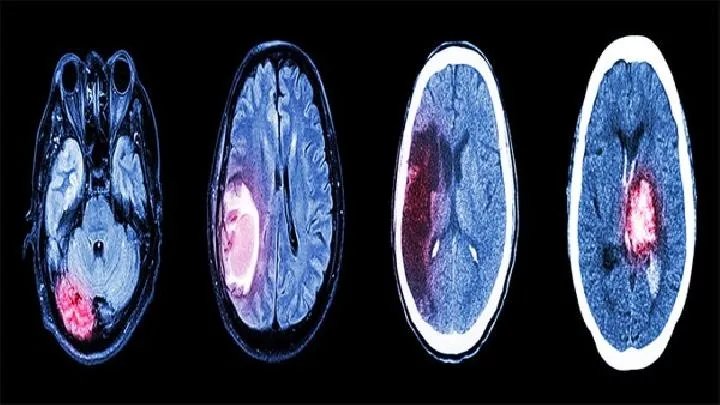

1.CT检查

CT显示梗死灶密度低,可明确病变的部位、形状和大小。较大的梗死灶可使脑室受压、变形和中线结构移位,但脑梗死发病4。6小时内,只有部分病例可见边界不清的轻微低密度灶,而大部分病例只能在24小时后显示边界清晰的低密度灶,小于5mm梗死灶后颅凹梗死不易CT皮质表面的梗死通常不会出现CT检测。

增强扫描可提高病变检出率和定性诊断率。出血性梗死CT大面积低密度区域有不规则斑片状高密度区域,与脑血肿的区别在于低密度区域较宽,出血灶散落在小面积。

2.MRI检查

MRI对脑梗死的检测极其敏感,对脑缺血性损伤的检测优于CT,缺血1小时内可发现早期脑缺血性损伤。

发病6小时后,几乎所有大梗死都可以被发现MRI显示,表现为Tl加权低信号T2加权高信号。